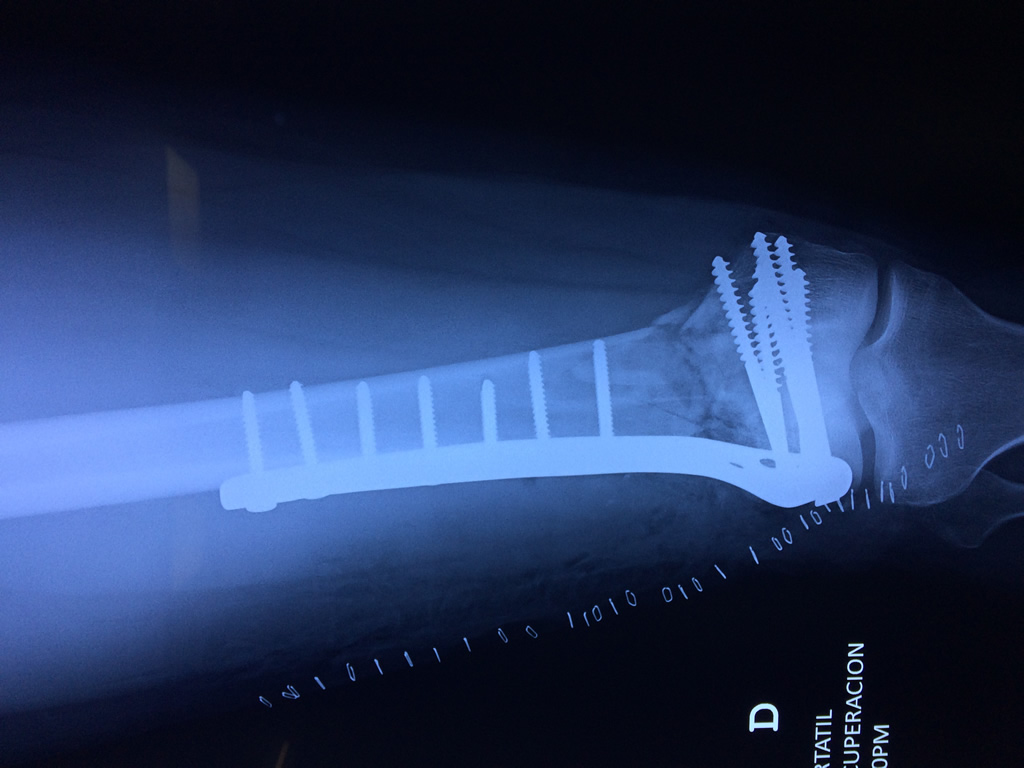

El fémur es el hueso del muslo, el segundo segmento del miembro inferior. Es el hueso más largo, fuerte y voluminoso del cuerpo humano.